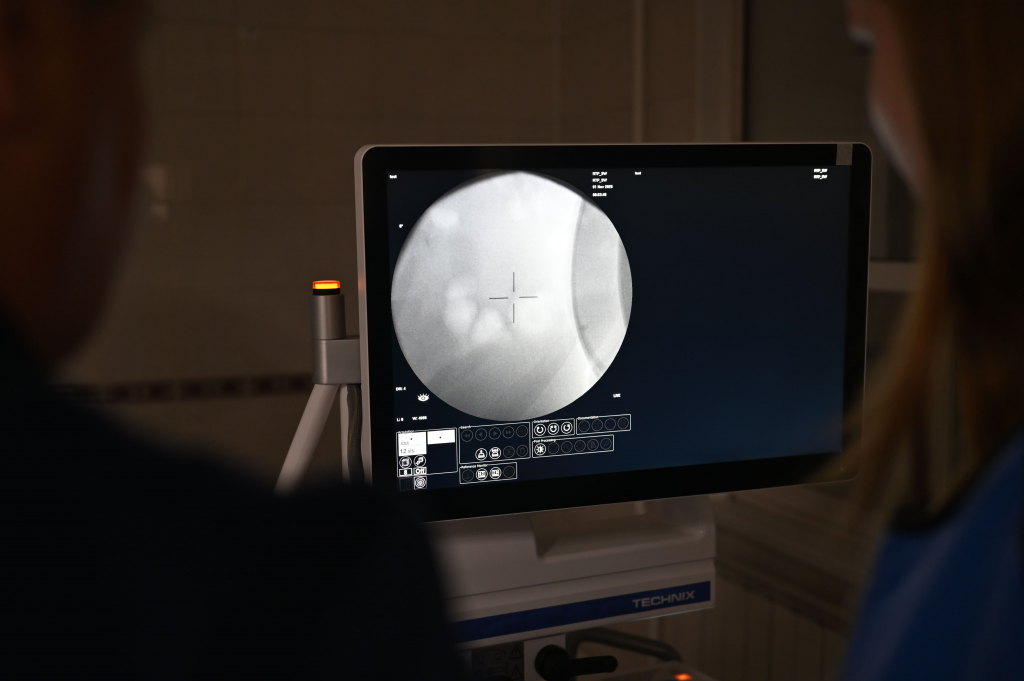

«Новый аппарат — это "золотой стандарт" в урологии. Система поддерживает совмещение рентгеновского и ультразвукового контроля в реальном времени, что обеспечивает точное наведение на камень, которое врач видит на мониторе», — рассказал заведующий отделением урологии поликлиники Городской клинической больницы № 14 Екатеринбурга Сергей Пристоленко.